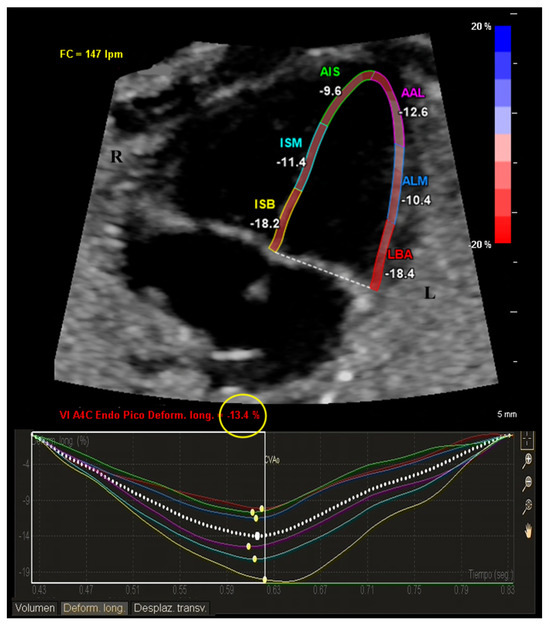

2.2. Ultrasound Acquisition

2.3. Analysis Protocol